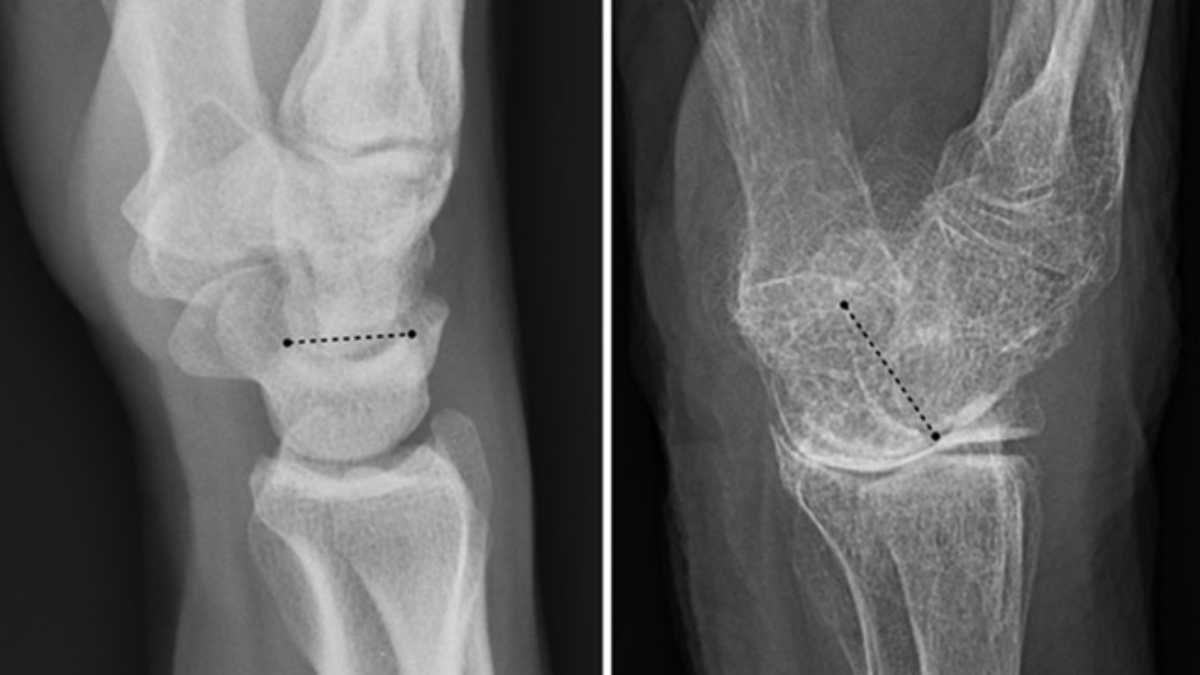

Si bien la osteoporosis es más común en las mujeres, las fracturas de columna o cadera que pueden causar son más peligrosas en los hombres Leer más